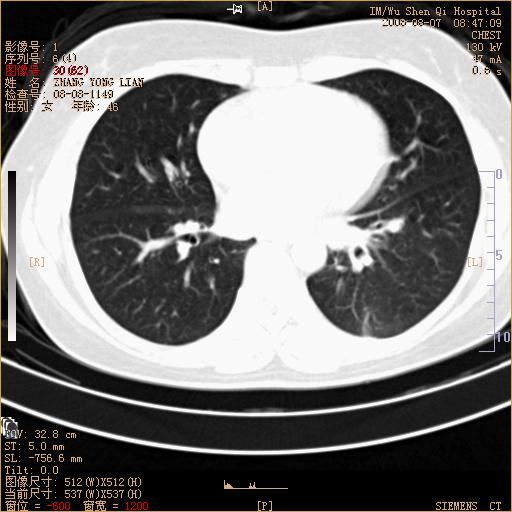

标题: CT15050:女,46岁,咳嗽胸痛一月余 [打印本页]

标题: CT15050:女,46岁,咳嗽胸痛一月余

纵隔窗没发全,左下肺近胸膜处结节。有长毛刺,纵隔淋巴结增大,不排除恶性病变。

考虑左肺下叶后基底段周围型肺癌伴纵隔淋巴结转移可能性大。

左下肺ca并纵隔及左肺门区淋巴结转移。

脾脏低密度结节转移不排除。

1)考虑左肺下叶后基底段周围型肺癌伴纵隔淋巴结转移。2)脾内低密度灶,性质待定;不排除转移瘤可能。

考虑左肺下叶后基底段周围型肺癌伴纵隔及肺门淋巴转移。